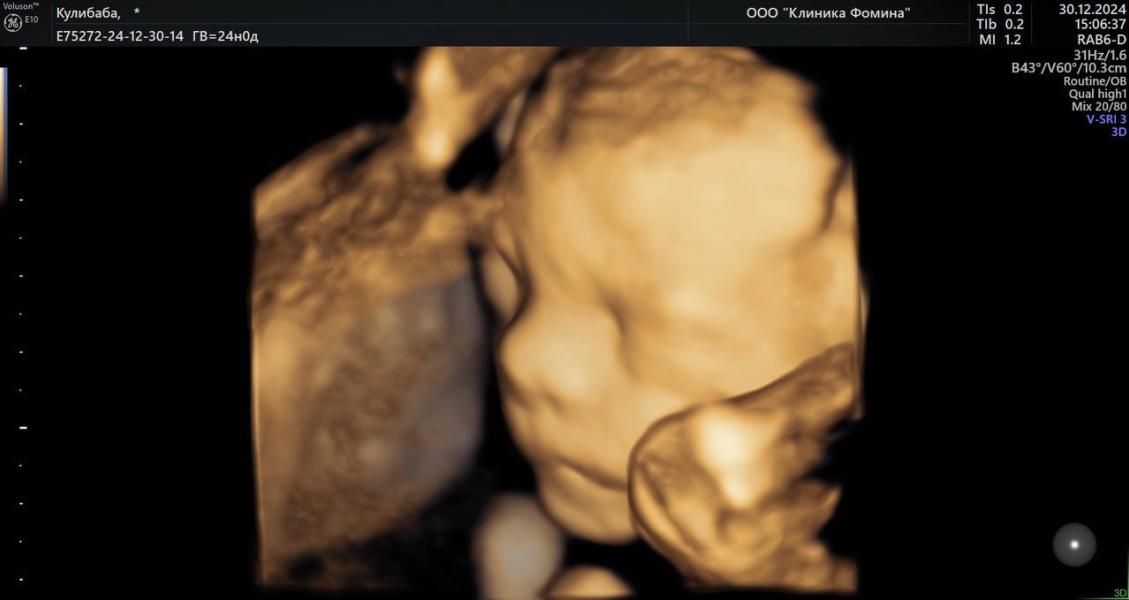

Впереди был второй скрининг, мы решили пройти его платно. И у нас появились прекрасные кадры нашей малышки с 3Д узи.

Она была красавицей, уже тогда увидели, что очень похожа на папу.

Делали в Клинике Фомина. УЗИ шло почти час, мне показали каждый орган, каждую клеточку. Все объяснили и рассказали.